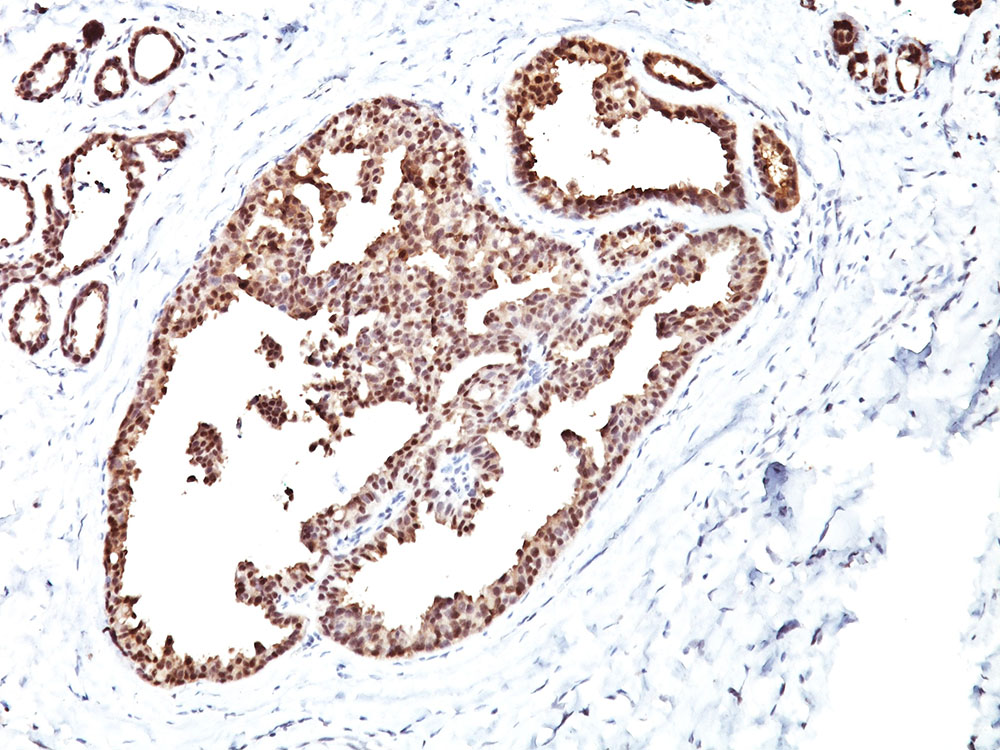

Formalin-fixed, paraffin-embedded human breast carcinoma stained with HSP60 MAb (LK1) |